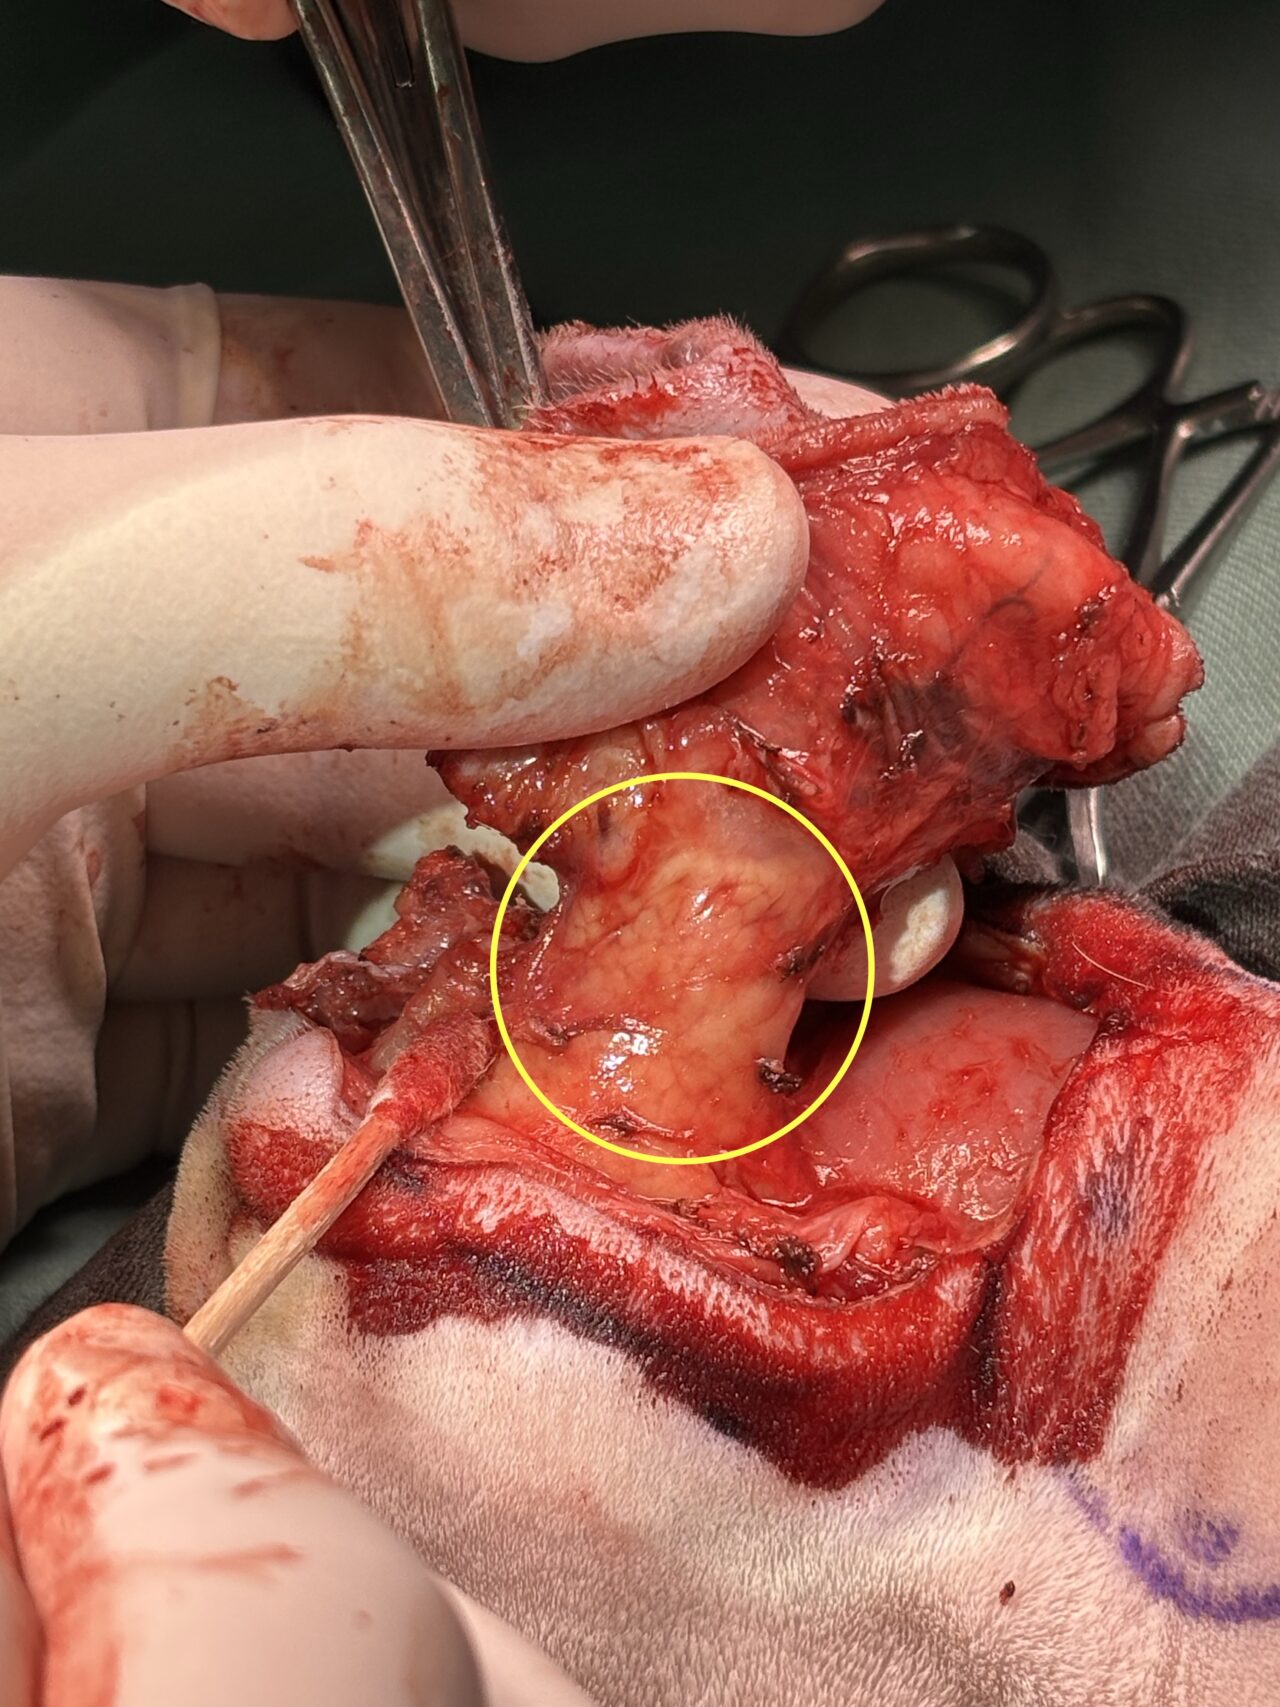

切除をすすめ、垂直耳道部分(黄色丸)を確認し、腫瘍が浸潤していないことを確認し、切除しました。

切除後です。黄色丸は残っている耳道です。